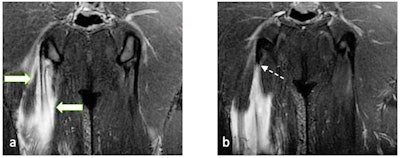

23-year-old male footballer with right semimembranosus muscle longitudinal split tear. (a) and (b) Coronal T2-weighted fat-saturated MRI of pelvis shows feathery edema in bipennate muscle fibers (arrows) converging on central tendon (white solid arrows). This demonstrates longitudinal split, with the proximal extent of tear extending almost up to the level of ischial tuberosity (white dashed arrow).Muscle injuries are frequent in football players, mostly in hamstrings, quadriceps, adductors, and calf muscles. Ultrasound is a helpful primary imaging modality, but MRI remains the mainstay in the diagnosis of muscle injuries, identifying precise anatomical location and pattern of injury that might range from interstitial edema without fibers distortion to more severe injury pattern with fibers and architecture distortion, laceration, and gap. The injury might involve one or more of these components: muscle fibers, myoaponeurosis/fascia, myotendinous junction, and tendon.